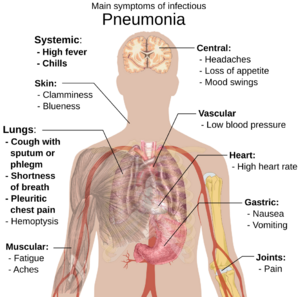

Pneumonia is a disease that affects your lungs and how you breathe. Your lungs have tiny air sacs called alveoli. They help your body get oxygen from the air you breathe. When you have pneumonia, these sacs get swollen and fill with fluid. This makes it hard for them to take in enough oxygen. So, it becomes hard to breathe. You might feel short of breath or have chest pain when you breathe. Pneumonia can be very serious, especially for certain people, even with medical care.

People with pneumonia usually have trouble breathing. They might also cough a lot or feel pain in their chest. The way doctors treat pneumonia depends on what caused it. If bacteria caused it, doctors can give you antibiotics to help you get better.